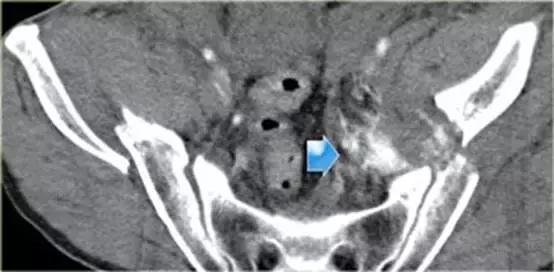

同一病人的CT常规增强检查

结果

有一个指向膀胱的骨盆骨折碎片。

膀胱直肠隐窝积液。

膀胱造影前后CT对比图像

膀胱中导尿管有对比剂, 膀胱直肠隐窝中也有渗出的对比剂。

‘磨牙征’ 提示腹膜外膀胱破裂。